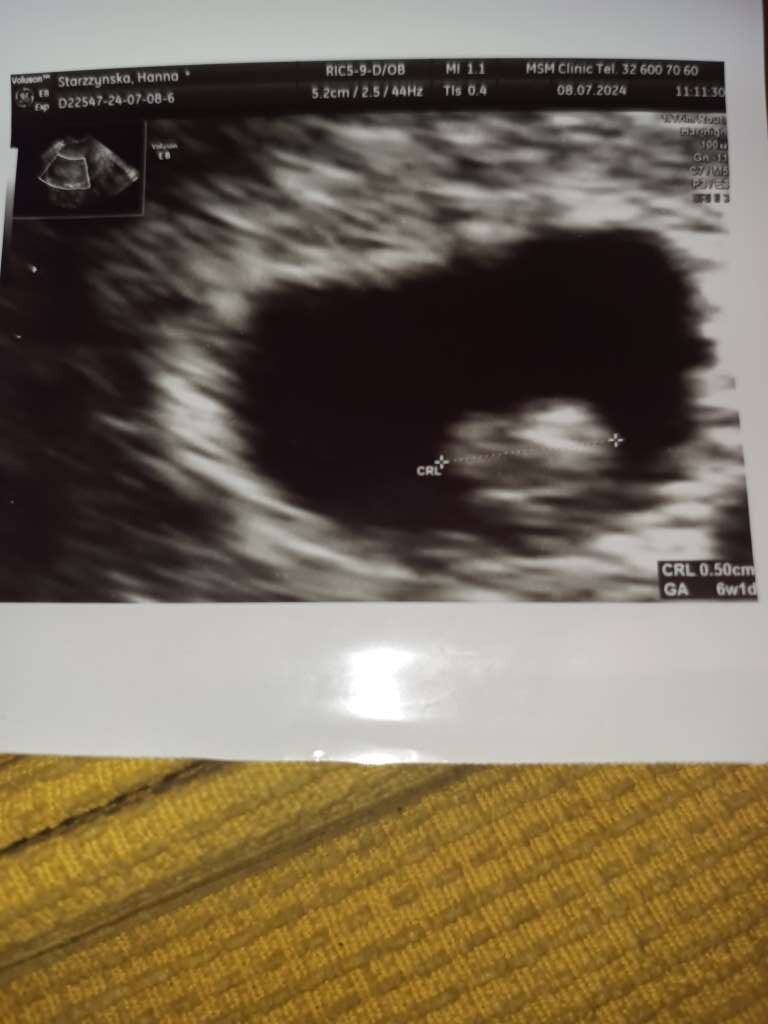

A to moje mala fasolinka, beta wystrzelona w kosmos a malutek ma 0,5 cm wczoraj nie wstawiłam bo czekałam na nowy tel.

• a3b513de-9c05-4535-921d-ba5975e08220.jpeg

a3b513de-9c05-4535-921d-ba5975e08220.jpeg

58,6 KB · Wyświetleń: 115